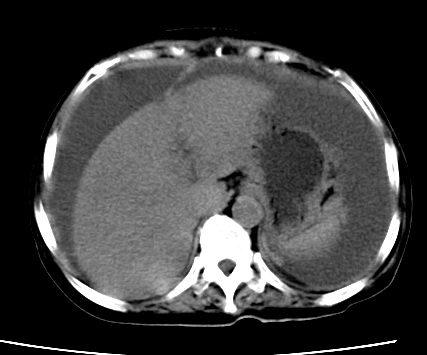

标题: CT23975:女61岁,腹部不适,明显消瘦

既往5年前卵巢癌行子宫及附件切除,右乳癌术后一年,考虑腹膜转移?

大量腹水,考虑腹膜转移。肝脏低密度灶。1囊肿,2转移。

1)结合病史,考虑腹膜及网膜转移瘤。2)肝脏多发性低密度灶,不排除转移瘤。3)大量腹水。

考虑卵巢癌行子宫术后复发,并肝、腹腔 、大网膜转移可能性大。

大量腹水。